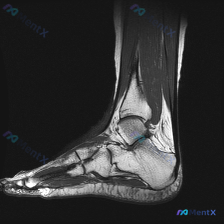

踝关节MRI读片病例分享,整理了完整分析思路 这是一例踝关节矢状位T2加权MRI,我把影像发现和分析思路整理出来,和大家一起讨论。 一、基本影像信息 这是踝关节MRI T2序列矢状位图像,可观察到胫骨远端、距骨、跟骨及周围软组织结构,核心阳性征象如下: 1. 骨骼关节改变:距骨穹窿(圆顶)可见明确局...

看到这个踝关节MRI的读片请求,问题是观察到的软组织积液,我整理了完整的影像和分析思路分享给大家。 病例影像基础信息 这是踝关节MRI矢状位T2序列图像,核心观察结果如下: 1. 骨骼系统:胫骨远端、距骨、跟骨、舟骨骨皮质完整,未见明确骨折线;距骨体及跟骨骨髓信号均匀,无明显水肿或硬化改变 2. 关...

今天给大家分享一张踝关节MRI矢状位T2加权影像的读片分析,病例本身并不复杂,但这种仅表现为少量积液的情况,临床其实很容易走偏,整理一下完整的思考过程给大家参考。 一、影像核心信息整理 这张是踝关节矢状位T2加权MRI,我们先把所有明确的影像信息理清楚: 1. 骨骼结构:胫骨远端、距骨、跟骨、舟骨骨...

看到一份很有代表性的踝关节MRI影像,整理了资料和分析思路分享给大家。 病例影像基本信息 这是一份踝关节矢状位T2加权像(T2WI),先给大家说下客观观察到的结果: 1. 解剖结构显示清晰:可以看到胫骨远端、距骨、跟骨、足舟骨及部分跖骨 2. 核心异常发现: - 胫距关节腔前方、后方可见明显T2高信...

看到一个有意思的踝关节病例,临床怀疑软骨异常,但单张MRI影像的表现和临床判断有矛盾,整理一下思路和大家分享。 一、现有病例与影像信息 本次提供的是踝关节MRI-T2序列轴位单张图像,已完成初步影像分析: 1. 影像基本表现: - 可见踝关节间隙及距下关节周围明显高信号积液影,提示关节腔内积液 -...

最近看到这例踝关节MRI读片讨论,问题是「图像中能观察到什么软组织液相关改变」,整理一下完整分析思路,分享给大家。 一、病例影像核心信息 这是踝关节MRI冠状位T2加权图像,核心发现如下: 1. 骨结构改变:胫骨远端、距骨、跟骨显影清晰,距骨穹窿内侧关节面可见局灶性高信号改变,边界清晰,呈楔形凹陷状...